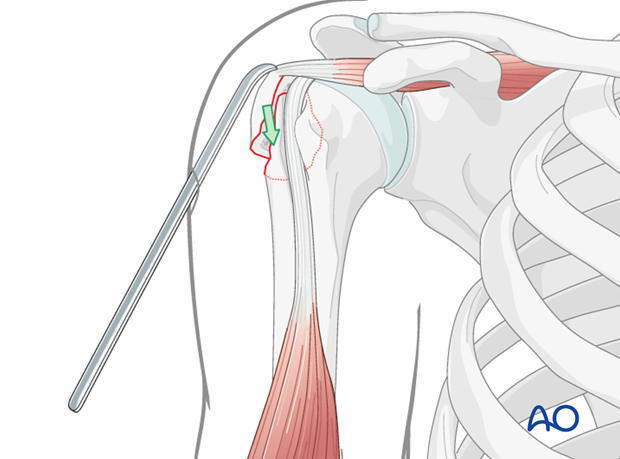

This image likely illustrates the initial exposure of the fracture site via the deltopectoral approach, revealing the displaced greater tuberosity fragment.

This image illustrates the use of a reduction instrument, likely a pointed reduction forceps, to manipulate and hold the greater tuberosity fragment in its anatomical position prior to definitive fixation.

This image demonstrates the temporary K-wire fixation maintaining the reduced greater tuberosity fragment, a common step before inserting definitive screws.